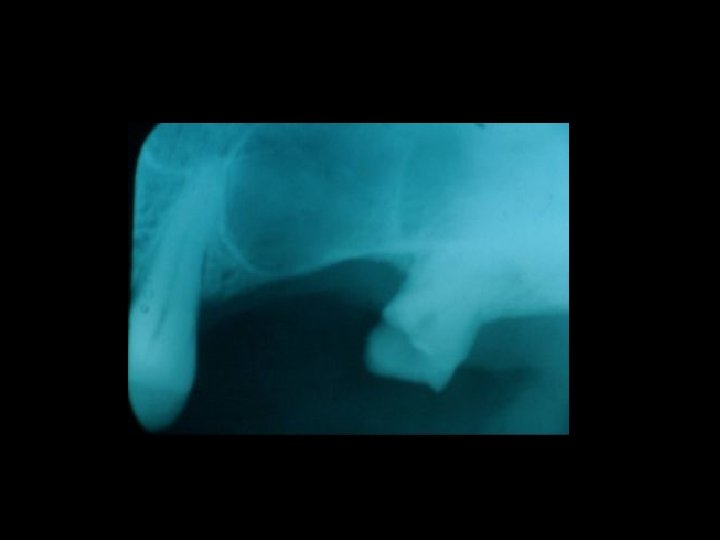

Responsabilità Ø Nel periodo pre-operatorio Ø Relativamente all’intervento Ø Nel periodo post-operatorio